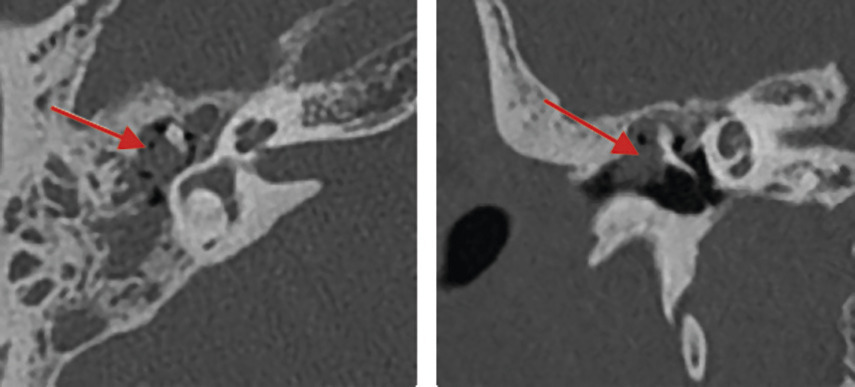

Cholestéatome au scanner : opacité nodulaire à contours convexes, responsable de lyses osseuses (mur de la logette : paroi de la caisse du tympan) et ossiculaires (fig. 3).

Si doute diagnostique surtout en postopératoire, l’IRM fait la distinction en cas de comblement, entre éventuel cholestéatome et rétention ou fibrose inflammatoire associée.

En faveur du premier : franc hypersignal sur la séquence de diffusion non rehaussé après injection de gadolinium, y compris sur les séquences tardives.